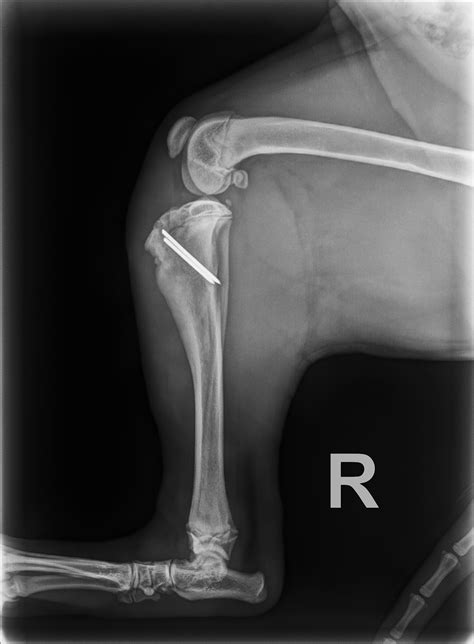

• Orthopedic Surgery: The hospital provides advanced orthopedic surgery for conditions such as hip dysplasia, cruciate ligament injuries, and fractures. The surgical team is experienced in performing complex procedures to restore mobility and function.

Fracture Repair — Warm Springs Pet Hospital

1403×1049